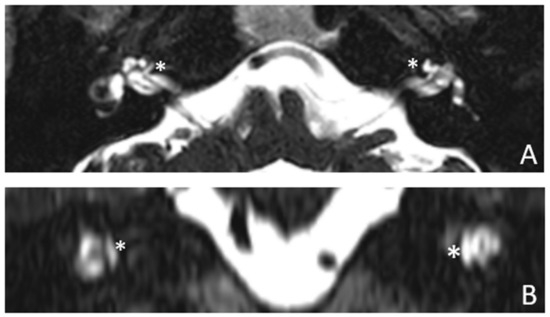

Patient #3, affected by otosclerosis: HL started as mild CHL, but she had a progression with a worsening of the bone threshold, probably due to cochlear evolution of the disorder. Even in this case, there was no indication for stapes surgery because of the communication between CSF and perilymph through the cavities. The images also show a superior semicircular canal deiscence (SSCD)on the left. CT and MR images show the bilateral cavities (Figure 5 and Figure 6).

Figure 6. MR images of patient #3 with otosclerosis and SSC dehiscence on the left side. MR cisternography: (A,B), axial plane. Note the fluid-signal in the newly formed cavity (white asterisk).